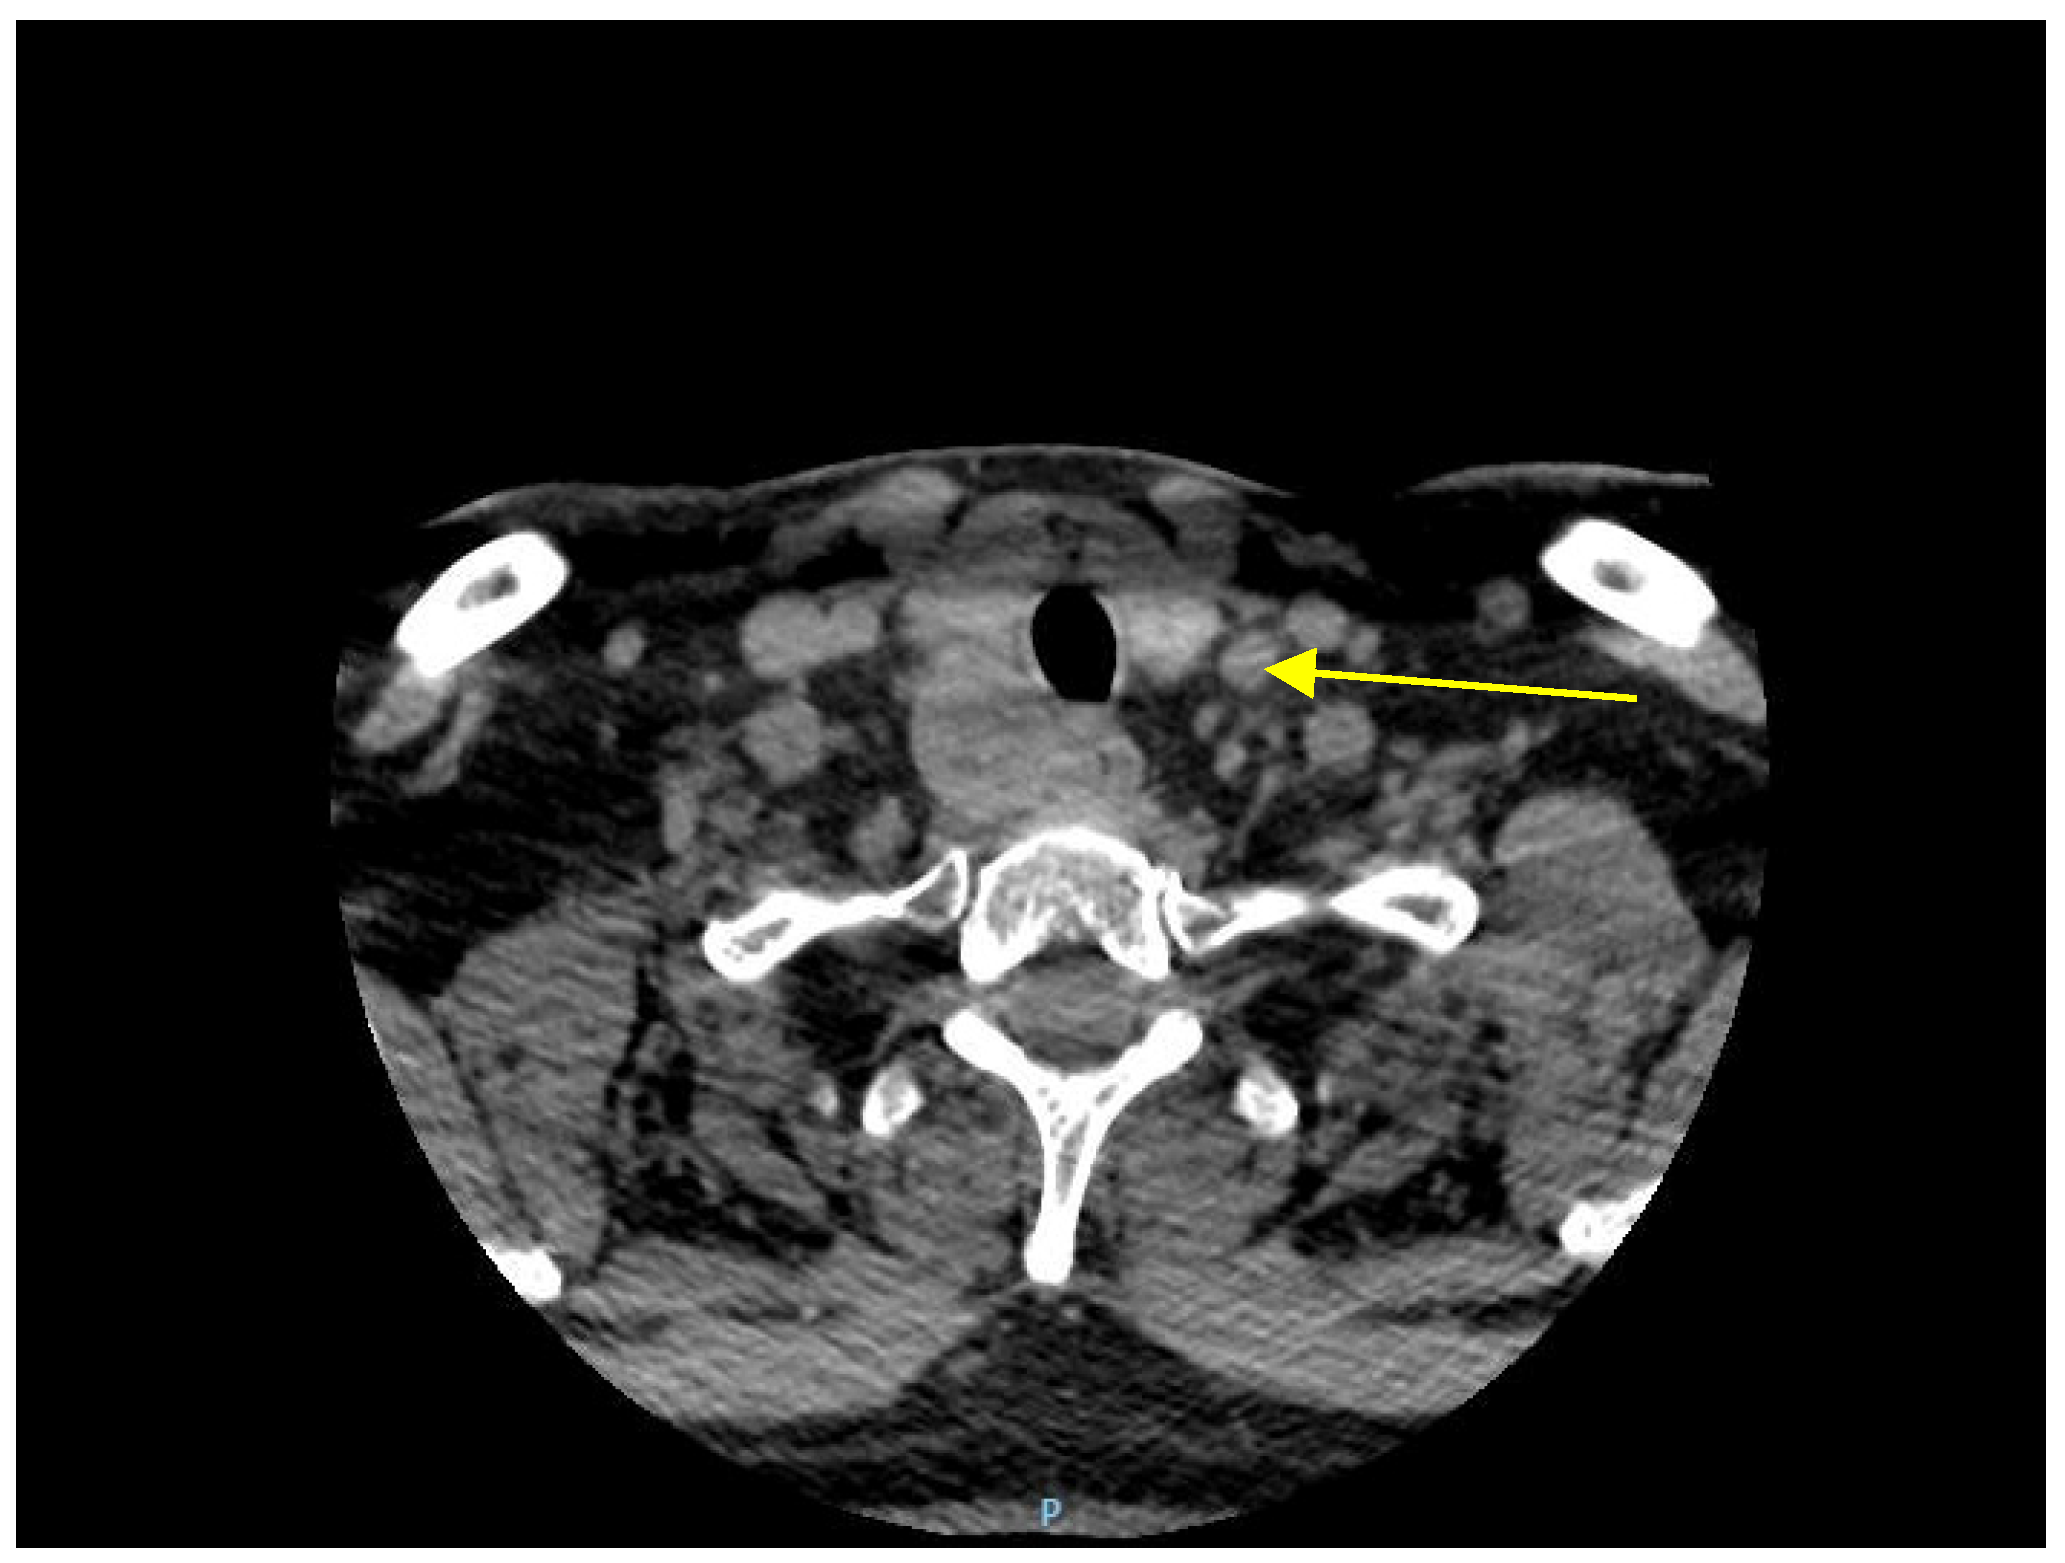

2.3. Imaging Findings